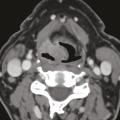

Bilan d’imagerie et orientation diagnostique des cancers des voies aérodigestives supérieures

Les voies aérodigestives supérieures (VADS) constituent la partie haute des systèmes respiratoire et digestif. Elles sont constituées de muqueuses, soutenues par des éléments musculaires complexes et des structures osseuses et cartilagineuses dont l’analyse fine est nécessaire afin de déterminer l’extension des lésions qui s’y…